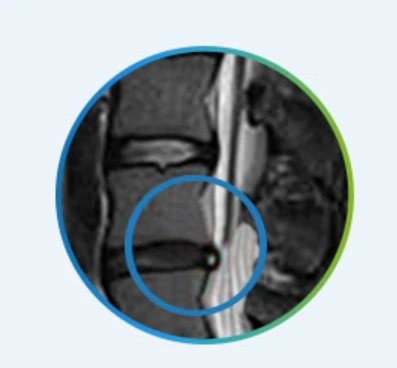

원래 디스크는 척추와 척추뼈 사이에서 우리 몸에 가해지는 충격을 흡수하고 척추의 움직임을 원활하게 해주는 중요한 역할을 하는데요. 이런 디스크에 심한 충격이나 오랜 시간 사용으로 인한 퇴행이나 손상으로 인해 디스크 안의 수핵이 밖으로 흘러나오면서 척추를 지나가는 신경을 압박하게 됩니다.

바로 이것이 우리들이 잘 알고 있는 허리디스크라고 부르는 허리디스크터짐입니다.